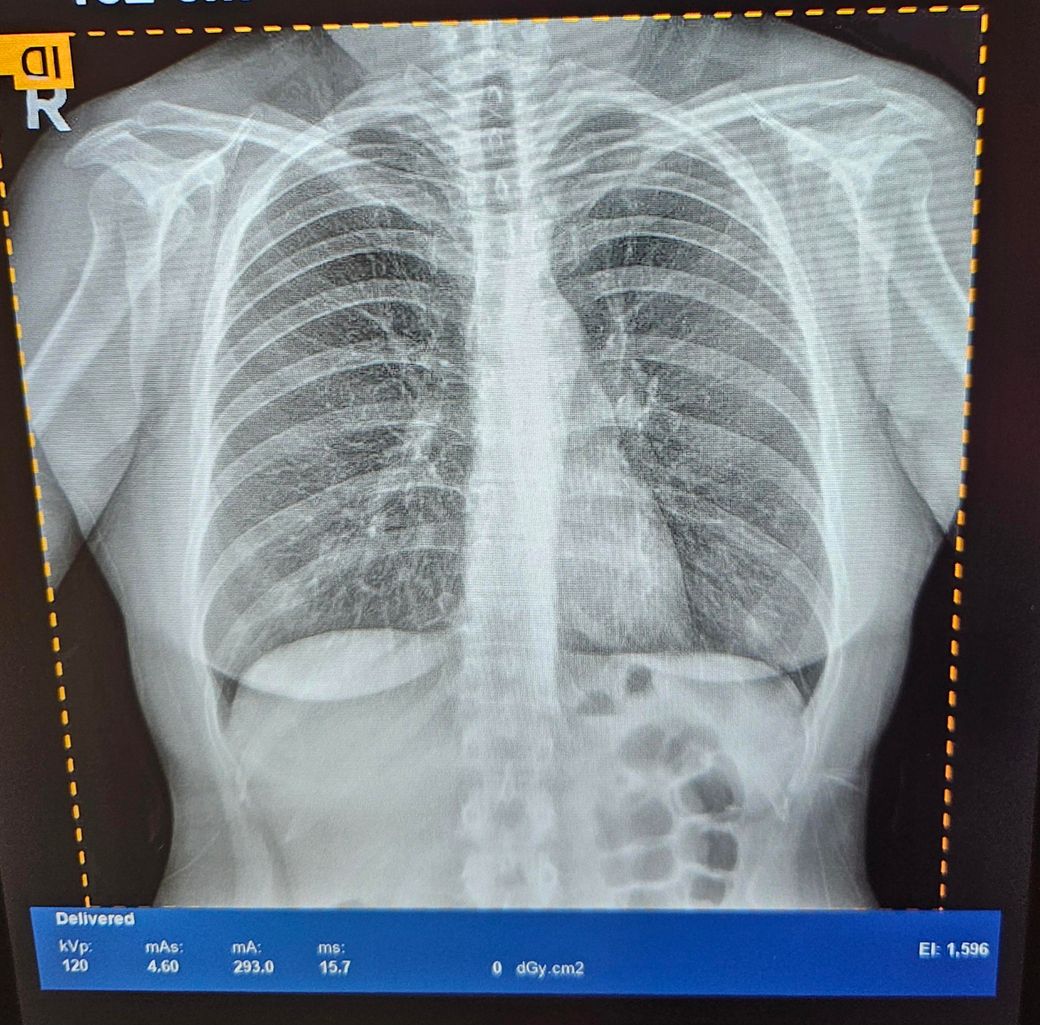

폐엑스레이(뿌연폐)사진좀 봐주세요

8월중순 코로나걸리고

2주뒤부터 기침가래가 심했습니다

그러고 두달가까이 가래가 계속 나와서

건강검진을 받았는데요

흉부엑스레이와 저선량흉부시티 찍었고

시티는 사진이 없지만 기관지에 가래가

끼어있다고 약처방받았어요

근데 제 엑스레이 사진이 다른분들 엑스레이사진보다 많이 뿌얘보이고 폐가 선명하지 않은거 같은데

장비문제인지 제 폐가 안좋아보이는건지

궁금합니다 판독부탁드립니다

CT를 같이 찍었으면 CT가 훨씬 정확하니까 CT 괜찮다고 하면 걱정할 필요없겠습니다.

X-ray 나빠보이지는 않네요,, 전체적으로 뿌옇게 보이는 것은 음영 정도나 화질의 문제일 가능성이 높아보입니다.

따라서 엑스레이에서 아주 이상한 소견이 아니라면 CT의 소견을 우선시하시면 됩니다

환자분의 경우 다른분과 비교해서 이상하다고 생각을 하실 수도 있겠지만

CT상 특별한 문제가 없다면 크게 걱정하지 않으셔도 됩니다

처방 받으신 약을 잘 드시고 담당선생님 진료를 잘 받으시면 됩니다.